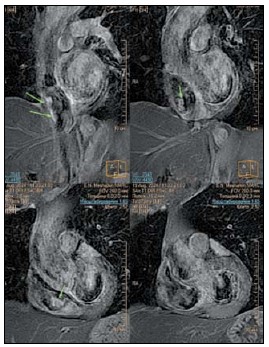

1. Рис. 1. УЗИ сердца с допплеровским режимом. Примечание: рисунок выполнен авторами

Тема

Тип Исследовательские инструменты

Посмотреть (28KB)